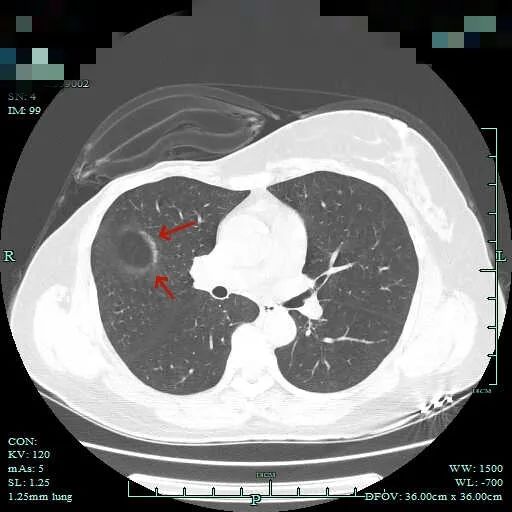

先来看在外院今年复查时的片子:

这个病灶在外院的报告是提示较既往的片子有增大进展的,但我们没有见到以前的影像。不过影像科报有增大进展,加上此次影像上看明显是混合密度,且边缘毛糙不平,细毛刺明显,血管穿行与进入也明显,何况紧贴叶间裂,若确实恶性,那是极容易胸膜种植转移的!这病灶放着那是睡不着觉的,所以我们建议其手术切除。术前还在想,如果术中发现胸腔内已经有种植转移,那么病灶单纯切除以取得病灶,指导术后综合治疗也是好的。